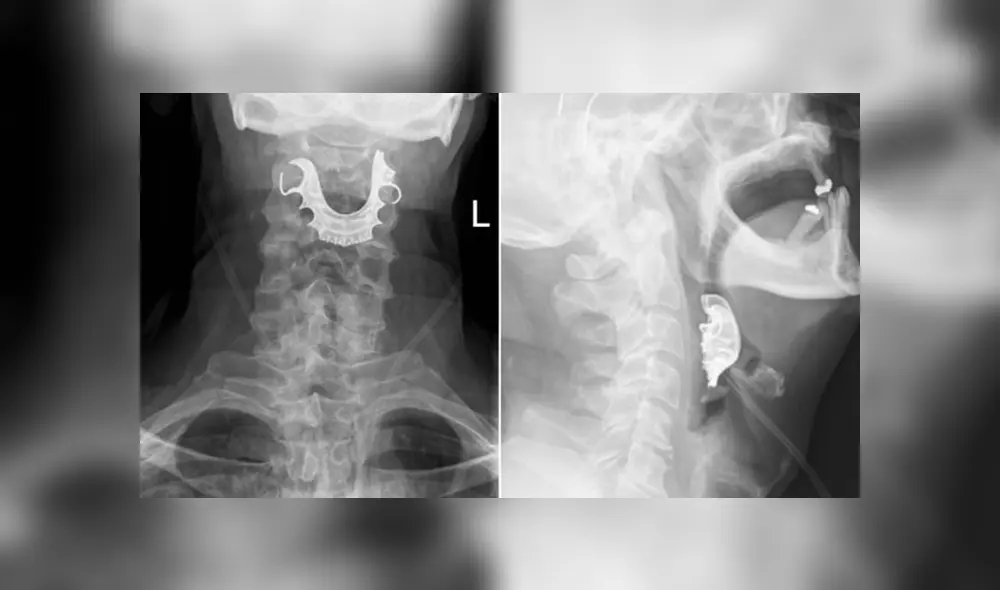

Un nuevo grupo de médicos revisó la garganta del paciente y ellos lograron detectar rápidamente que algo se alojaba en su laringe. Y fue entonces cuando él recordó que sus dentaduras postizas parciales se habían perdido misteriosamente apenas una semana antes.

De inmediato, los especialistas supieron que era altamente probable que el hombre había inhalado sus dentaduras al ser intubado.